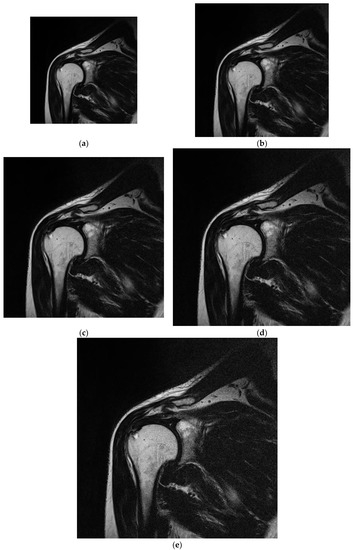

Figure 4.

Sample analyzed images acquired for matrices with various sizes under the same FOV. (a) 256 × 256; (b) 320 × 320; (c) 384 × 384; (d) 448 × 448; (e) 512 × 512.